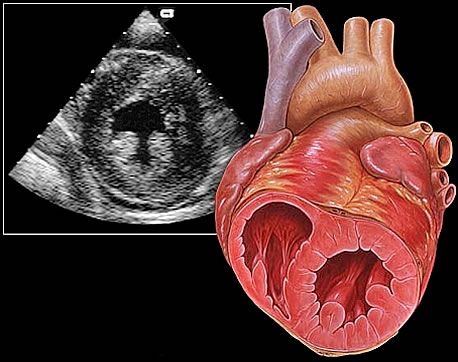

W kręgu zainteresowań pozostają: kardiologia ogólna, choroby wewnętrzne, diagnostyka obrazowa ( USG serca ), intensywna terapia kardiologiczna, mechaniczne wspomaganie krążenia.

* USG - echo serca